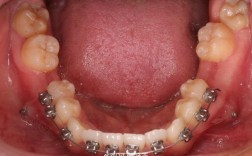

上下颌各拔第一前磨牙(最常见模式)

拔牙牙位(FDI编号):上颌14、24(右侧/左侧第一前磨牙),下颌34、44(右侧/左侧第一前磨牙)。

优势:第一前磨牙位于牙弓中段,拔除后既能提供足够的前牙内收空间,又不会对前牙区(美观关键区)和后牙区(咀嚼功能区)造成过大影响,且邻牙(尖牙和第二前磨牙)易于移动,稳定性好。